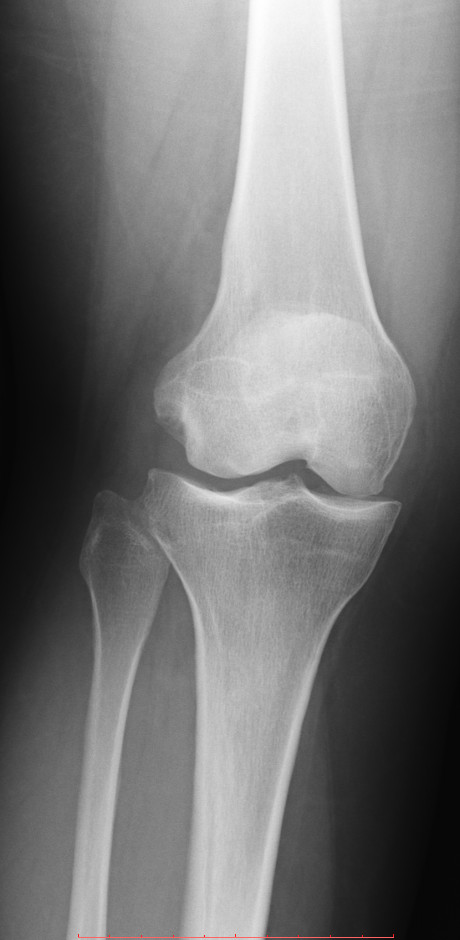

Женщина 1982 года, боль в правом коленном суставе в течении 2 лет, периодически лечит (подкалывает в сустав что-то, не помнит препарат).

Не нравится латеральный мыщелок правой бедренной кости, интересует ваше мнение коллеги?

Мыщелок как мыщелок. Артроз как артроз (без стадии!, коллеги). Отметил бы выраженную дисконгруэнтность суставных поверхностей.

На мой взгляд, есть некоторая гипоплазия латеральных мыщелков бедренных костей. Кажется, собственного названия она не имеет, но в целом может быть предрасполагающим фактором.

Судя по медиальным щелям - повреждены медиальные мениски.

Что же, печально. Случаи интересные отправляются снова в безвестность... Гипоплазия латеральных мыщелков или гиперплазия здесь мыщелков медиальных? Или тазобедренные суставы нужно всё-таки посмотреть - какие они, что необычного в них есть или нет? Несколько подобных картинок встречать и мне приходилось. На взгляд мыщелки асимметричны, но хрящ суставной не изменён (ширина щели нормальна) и изменения на другой стороне симметричны - это главное.) Вот в чём вопрос - будут ли за такой возраст изменения компенсаторные - компенсирующие такую несимметричность мыщелков или не будет их, независимо от прямохождения и нагрузки несоразмерной, местами избыточной? Опытный глаз одного доктора (при меньшей асимметрии) дисплазию мне подсказал. Я её тогда не заключал. А мыщелков размеры и несоразмерность уже навстречал... Кто прав? Кто в таком случае знает, как правильно всё угадать?..